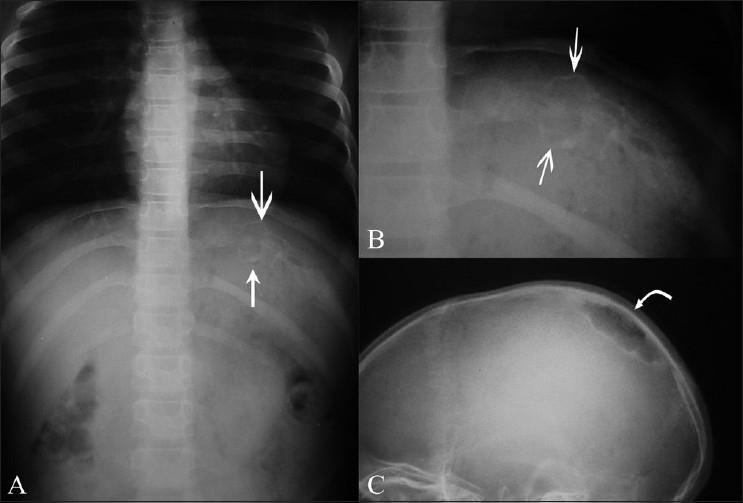

All patients had clinical signs and symptoms localized to the site of involvement, whether it was the sternum, sternoclavicular joints, or ribs. CT scan revealed sternal destruction in three patients and osteolytic lesions with sclerosis of the articular surfaces of the sternoclavicular joints in two patients. In five patients with rib lesions, USG elegantly demonstrated the bone destruction underlying the cold abscess. All cases were confirmed to be of tuberculous origin by pathology studies of the aspirated/curetted material, obtained by CT / USG guidance.

Tuberculous etiology should be considered for patients presenting with atypical sites of skeletal inflammation. CT scan plays an important role in the evaluation of these patients. However, the use of USG for demonstrating rib destruction in a chest wall cold abscess has so far been under-emphasized, as has been the role of CT and USG guided aspiration in confirming the aetiology.

所有患者的临床体征和症状均局限于受累部位,无论是胸骨、胸锁关节还是肋骨。CT扫描显示3例患者胸骨破坏,2例患者胸锁关节面出现骨质溶解伴硬化。在5例肋骨病变患者中,超声清晰地显示了寒性脓肿下方的骨质破坏。通过CT/超声引导下获取的抽吸/刮除材料的病理研究,所有病例均确诊为结核起源。

对于出现骨骼炎症非典型部位的患者,应考虑结核病因。CT扫描在评估这些患者中起重要作用。然而,超声在显示胸壁寒性脓肿中肋骨破坏方面的应用至今未得到充分重视,CT和超声引导下抽吸在确诊病因方面的作用也未得到充分重视。